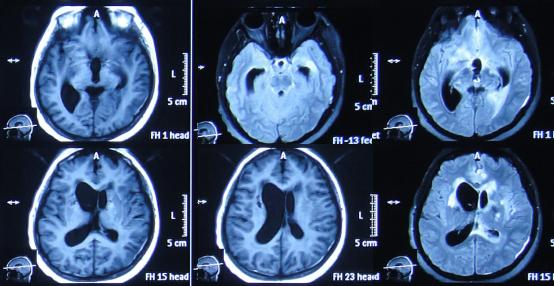

患者于2015年7月31日,无明显诱因突发头痛发热症状,体温升高至38.6℃,因自行服药3天后无改善即2015年8月3日,就诊并住入第1家的位于四川省成都市某军医院的神经内科,查头MRI示“右侧小脑半球结节影,环性强化”(图-1)。

图-1:2015年8月3日头部MRI